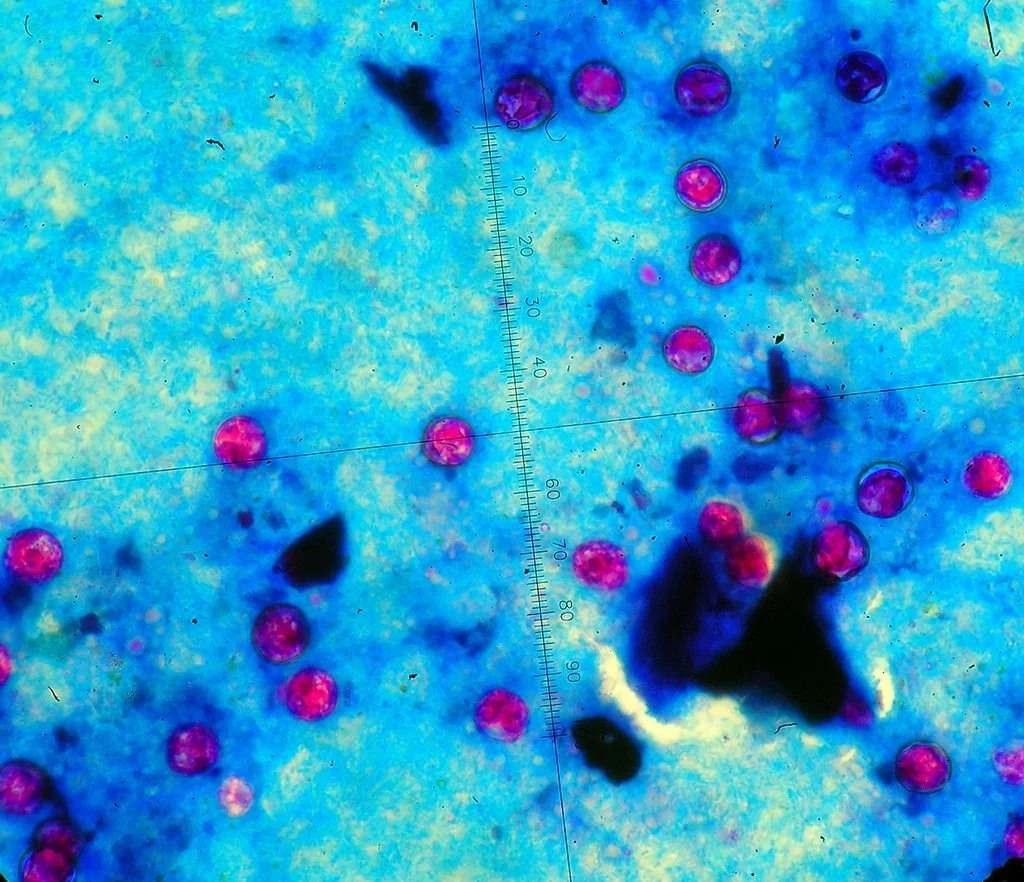

2013년 6월 중순, 몇 명의 미국인이 심한 설사를 하기 시작했다. 설사는 말 그대로 물에 변이 조금 섞여 있는 수준이었고, 복통도 동반됐다. 밥맛도 없었으니 살이 빠지는 건 당연했다. 한두 명이 하면 ‘개인적 일탈’로 치부되지만, 수십 명 수준이 되면 ‘사회적 현상’이 된다. 이때의 설사가 그랬다. 6월 26일이 됐을 때 설사로 고생하는 환자는 285명으로 늘었고, 입원한 환자도 18명이나 됐다. 한 주(州)에 몰려 있다면 원인이 되는 식당을 찾으면 됐지만, 환자들의 거주지는 11개 주에 퍼져 있었다. 보건 당국은 갑작스럽게 발생한 이 사태의 원인을 찾으려고 동분서주했다. 가장 가능성이 높았던 세균에서는 음성 반응이 나왔고, 바이러스는 당연히 아니었다. 그렇다면 남은 건 기생충밖에 없었다. 혹시나 싶어 와포자충(『기생충 열전』 참조)을 의심해 항산성 염색을 해 봤다. 뭔가가 나왔다. 그런데 와포자충이 아닌 다른 기생충이 분홍색으로 빛나고 있었다. 원포자충(싸이클로스포라, Cyclospora)이었다.

3-1.jpg?type=w1200 분홍색 동그라미가 원표자충이다